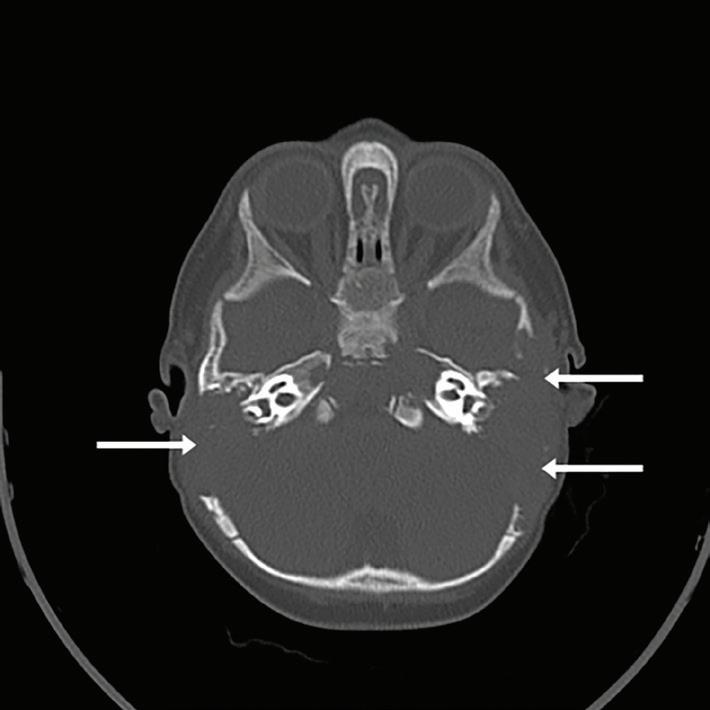

Computed tomography (CT) of the head showed extensive facial, skull base, and calvarial lytic lesions with bony destruction and soft-tissue masses consistent with LCH. There was extensive bilateral lytic destruction involving the temporal bones, with almost complete destructive changes of the mastoid portion and extension up to the external auditory canal (figure 1). There were also bilateral lesions of the petrous temporal bones.

Figure 1. CT scan shows extensive bilateral lytic destruction involving the temporal bone with almost complete destruction of the mastoid portion. Figure 2. MRI shows mastoid air cells and middle ear cavities completely replaced by LCH.

Imaging modalities such as plain radiography, CT, MRI, positron emission tomography (PET), and bone scan are used to identify, stage, and monitor LCH. CT is useful in delineating bony destruction, whereas MRI is useful in demonstrating soft-tissue and intracranial extension. Therefore, CT and MRI were both used in this child. Bone scan or full skeletal survey is performed to stage LCH. PET has a potential to identify extraskeletal LCH and to evaluate response to treatment.